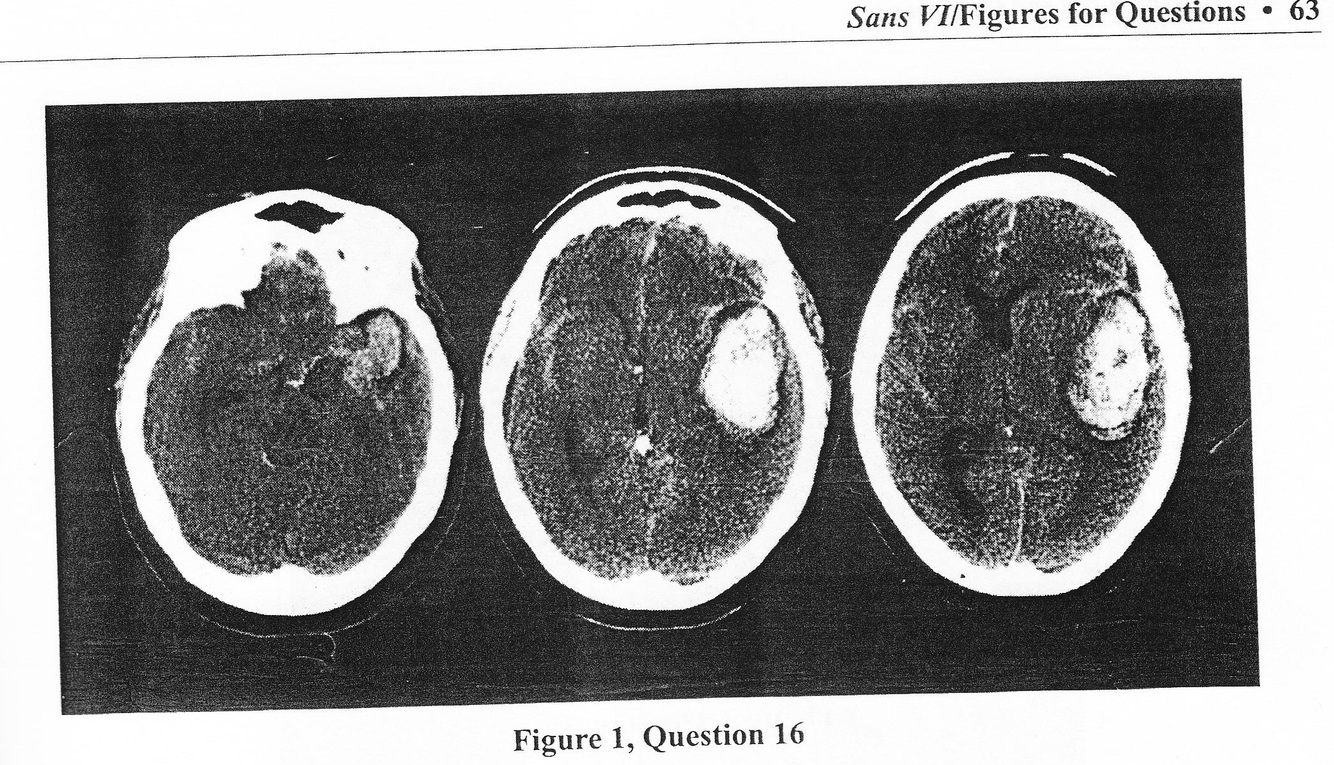

A 41-year-old female with no significant medical history undergoes laparoscopic cholecystectomy without incident. In the recovery room she begins to camplain of left-sided headache and becomes progressively lethargic. Right-sided movements become sluggish, oxygen saturation drops, and she is reintubated. You are called from the CT scanner to view the cranial images (Figure 1). Your examination of the patient 30 minutes after symptom onset reveals decorticate right-seide posturing, withdrawl to pain on the left side, a dilated nonreactive left pupil and, a blood pressure of 160/100 mmHg. The most likely diagnosis and best course of therapy is :

a. Hypertensive hemorrhage. Begin immediately aggresive intravenous therapy to reduce systemic blood pressure

b. Amyloid angiopathy. Begin hyperventilation and consider stereotatctic biopsy of parenchymal wall of hematoma to assess for presence of amyloid deposition in vessel walls and brain parenchyme

c. Arterial pressure hemorrhage. Begin hyperventilation, secure bladder drainage with catheter and give mannitol while transporting patient to the operating room form emergent clot evacuation and plans for possible engagement of aneurysm, vascular malformation or tumor.

d. Hemorrhage, etiology indeterminant. Place intracranial pressure monitor, begin aggresive treatment to lower intracranial pressure and blood pressure and move the patient to intensive care unit with plans for angiography.